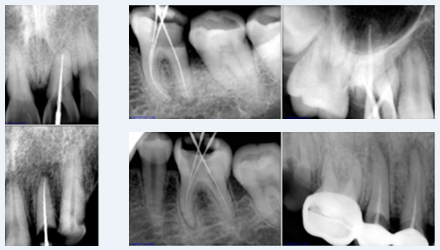

X-ray

User friendly working interface that was designed and developed specifically for radiological diagnosis. It is common imaging platform for all our digital dental system.